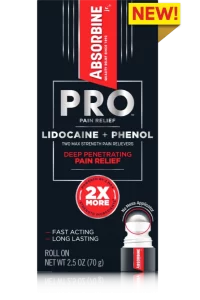

Pro Pain Relief Cream

Apply like a Pro: Cream guaranteed

to cover to the source of pain

WITH 2 MAXIMUM STRENGTH ANESTHETICS

Lidocaine + Phenol

Lidocaine Works Harder with Phenol to Provide the Strongest Numbing Pain Relief on the Market*

Pain Relief Cream With Lidocaine & Phenol

Phenol is a numbing agent and also a penetration enhancing ingredient. “Penetration enhancers (CPE)” are proven to increase the transport of drugs across the skin layers and help Lidocaine work even harder. These two ingredients combine for the Maximum Numbing Pain Relief Available without a Prescription for long lasting and deep penetrating pain relief.

Nothing

numbs pain more

without a prescription*

Easy to apply targeted relief

Deep penetrating relief to numb away pain

Fast-cooling power

Active Ingredients

Lidocaine belongs to the family of medicines called local anesthetics. This medicine is a numbing agent that prevents pain by blocking the signals at the nerve endings in the skin. It’s deep penetrating and fast acting. 4% Lidocaine is the maximum strength available without a prescription.

Phenol helps block the channels needed to initiate and transmit pain signals and suppresses some blood flow to the affected area, which can also help to interrupt pain and inflammation cycles. And because Phenol is a penetration enhancer and readily absorbed through the skin, it helps Lidocaine start to work quicker and deeper than it could on its own.

Inactive Ingredients

acrylates/C10-30 alkyl acrylate crosspolymer, aloe barbadensis leaf juice, aminomethyl propanol, bisabolol, cetearyl alcohol, ceteth-20 phosphate, cinnamomum camphora (camphor) leaf oil, dicetyl phosphate, disodium EDTA, ethylhexylglycerin, fragrance, glyceryl stearate, mentha arvensis leaf oil, methylparaben, SD alcohol 40, stealth-21, water, zingiber officinale (ginger) root extract